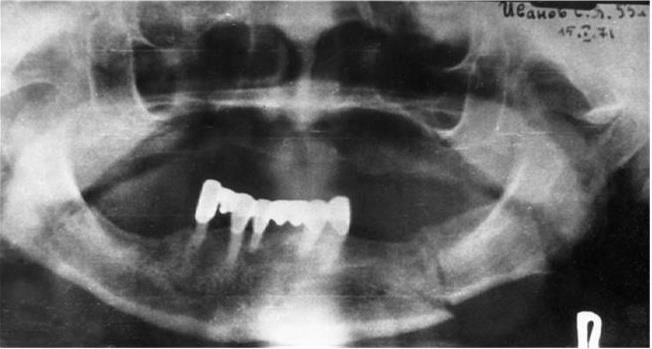

Рис. 5. Ортопантомограмма нижней челюсти при множественном переломе

Используют также панорамную рентгенографию и, особенно, ортопантомографию нижней челюсти. Преимущество этого метода – возможность быстро получить ценную диагностическую информацию о состоянии зубов и нижней челюсти (при панорамной рентгенографии – особенно в переднем отделе челюсти).

Ортопантомографическое исследование позволяет на одном снимке проследить за изменениями, возникшими в результате перелома нижней челюсти на всем ее протяжении (рис. 5).